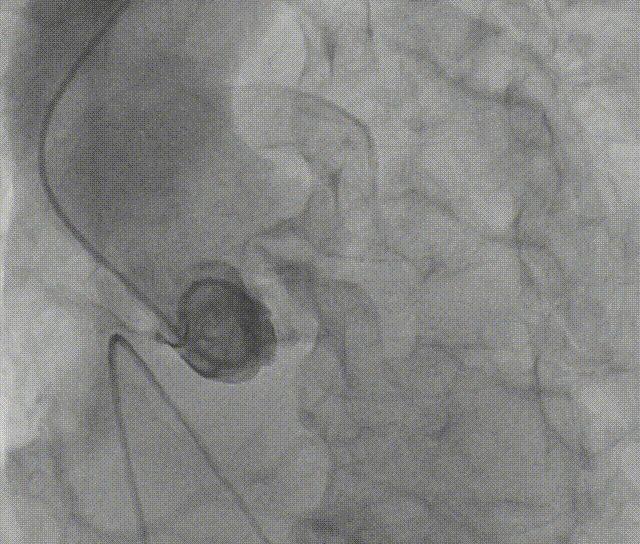

通过支撑导丝,送入26mm SAPIEN 3瓣膜,使用独特调弯功能,保证安全过弓并成功跨瓣;调整至共平面角度,瓣膜到位,快速起搏下-2cc精准释放瓣膜。

图片

原体积后扩。

出导丝后,造影超声结果均显示瓣膜工作良好,瓣膜释放后流入/流出比例=20:80,术后导管测量无压差,经胸超声检测无瓣周漏、无起搏器植入、无并发症,手术成功。